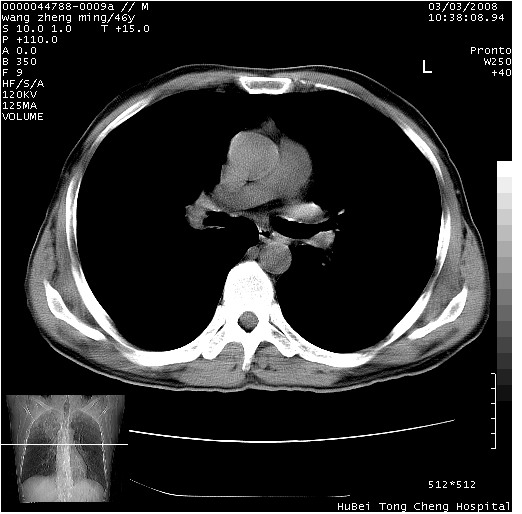

以下是引用卜一在2008-3-22 1:37:00的发言:[br]右肺实质性肿块,边缘不整,明显见毛刺征 分叶征及胸膜凹陷征,右上叶支气管明显变窄,远端散在的片状 斑片状实变影。另:左肺门较大肿块,支气管受累 变窄,远侧见阻塞性肺炎。纵隔内见肿大淋巴结。多考虑:右肺周围性肺癌伴左肺门 纵隔淋巴结转移!